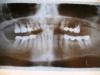

Olga2 Опубликовано 22 июня, 2009 Поделиться Опубликовано 22 июня, 2009 (изменено) Уважаемые врачи!Посоветуйте, пожалуйста,1.По лечению пародонтита. Снимок пересняла на фотоаппарат. Воспаление десны между 2 и 3 зубами справа ( 42 и 43,кажется) и там же дальше, между последним и предпоследним.Пила антибиотик.Сняли сейчас зубной налет и камень.(Ценник профессиональной гигиены зубов при патологии пародонта составил 5696руб). Далее врач предлагает по плану –ирригацию всех 26 зубов(?) (5300 руб),и этап 3- аппарат Вектор тоже все зубы (8420 руб). Это как бы профилактические мероприятия по снятию воспаления, а далее посмотрим. Сделать томографический снимок на 3-х мерном компьютерном дентальном томографе GALILEOS (5000руб)Ценник не очень понравился. Так ли все необходимо? И, что на все зубы,а не там где карманы? Может, попустить хотя бы один этап или сразу идти и сделать кюретаж? Или Вектором лучше? Не пойму, столкнулась первый раз2. По снимку – есть ли киста на последнем зубе слева, которая заходит в гайморову полость(так сказали) и является поэтому очень опасной. Справа, на последнем зубе кисту вижу. Попробую снять коронку и перелечить зуб-дополнительный вопрос – стоит ли или сразу удалить?Очень волнует ваше мнение.Вы мне уже как-то здорово помогли – зуб был спасен.С уважением,Ольга Изменено 22 июня, 2009 пользователем Olga2 Ссылка на комментарий

Bier Опубликовано 22 июня, 2009 Поделиться Опубликовано 22 июня, 2009 вы снимок неправильно расположили. Буква L должна быть справа.киста есть и на левом и на правом верхнем зубах. Мое мнение - удалять. нижние фронтальные зубы на выход. Никакие векторы им не помогут. Жизнь их скоро закончится. Если удалить сейчас - останется хоть костная ткань вокруг других зубов. Ссылка на комментарий

Снежана Опубликовано 23 июня, 2009 Поделиться Опубликовано 23 июня, 2009 Спасибо! С кистами понятно. Дико жалко -мост поставлен чуть больше года назад!И все-таки, неужели нет ничего более позитивного?Подсадка костной ткани под передние зубы не спасет их?Откликнитесь оптимисты!вот знаете, на этом снимке так мало видно, или у меня вдруг зрение испортилось, не знаю... нужно сделать несколько прицельных снимков, чтобы точно увидеть уровень кости. Подсадка вполне может отсрочить удаление этих зубов. Ссылка на комментарий